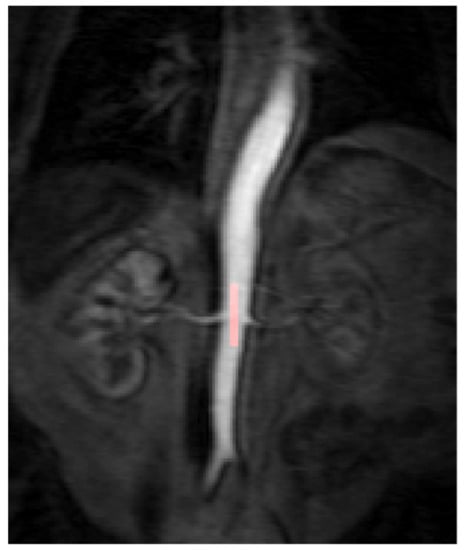

2.3. Post DCE-MRI Acquisition Image Analysis

All DCE-MRI imaging data were anonymised and post-processed using the software Platform for Research in Medical Imaging Version 0.4 (PMI 0.4) [15]. PMI was used to draw a region of interest (ROI) in the descending aorta and each of the tumours in order to obtain the arterial input function (AIF) and the corresponding tumour perfusion curve. The target tumour lesions identified for each patient within the abdomen and pelvis were segmented by two independent readers (both radiologists) who were blinded to the treatment outcomes and to the other reader’s segmentations. This was repeated for each of the 3 DCE-MRI time points (baseline, 4 weeks and 10 weeks) per patient. To calculate the AIF, a ROI was drawn over the abdominal aorta at the level of the ostia of the renal arteries (Figure 1). For consistency the ROIs were drawn in the phase of the peak contrast enhancement within the abdominal aorta for all patients. The ROI was optimised further to include only voxels that had a peak relative signal intensity change between the 95th and 100th percentile of the signal change maximum. This reproducible thresholding technique was used to reduce the likelihood of inflow or partial voluming effects and has been utilised in previous studies [18].

Figure 1. The arterial input function (AIF) region of interest (ROI) was manually drawn inside the aorta at the approximate level of the origin of the vascular pedicles of the kidneys in the dynamic series. The AIF area was optimised further to include only voxels that had a peak relative signal intensity change between the 95th and 100th percentile of the signal change maximum.